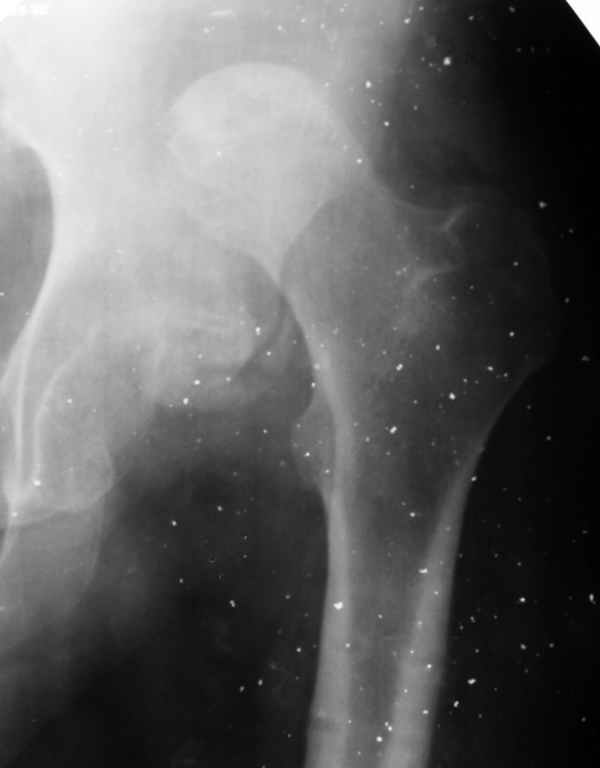

Здравствуйте. К нам поступил мальчик 15 лет с застарелым 7-месячным вывихом бедра из области. Травма мотоциклетная, при поступлении в больницу по месту жительства диагностирован перелом диафиза бедра и не распознан вывих бедра с этой же стороны.

Бедро было синтезировано пластиной и успешно срослось. Как поступить сейчас с вывихом? По КТ видны интерпонированные отломки, впечатление что это фрагменты головки бедра. Поделитесь, пожалуста, опытом. Спасибо.

What happened with femoral head?AVN?Plain x ray uncertain.

По-моему варианты с вправлением вывиха бесперспективны, вследствие явных признаков (КТ) асептического некроза головки. Все равно повторной операции - эндопротезирования - не избежать. А оперировать по старым рубцам потом будет сложнее. Поэтому, целесообразным представляется все-таки первичное тотальное эндопротезирование. Учитывая срок травмы и возраст, думаю, удастся компенсировать укорочение одномоментно. В противном случае лучшие годы жизни 15-20 лет парень может провести инвалидом и упустить массу возможностей. Жалко.

Думается, в данном случае необходимо приложить усилия к сохранению проксимального отдела бедра, что предполагает низведения головки до уровня впадины спицестержневым аппаратом с последующим открытым вправлением вывиха (несмотря на перспективу АВН головки).

Фрагменты в проекции вертлужной впадины кажутся задненижним сектором голоки бедра